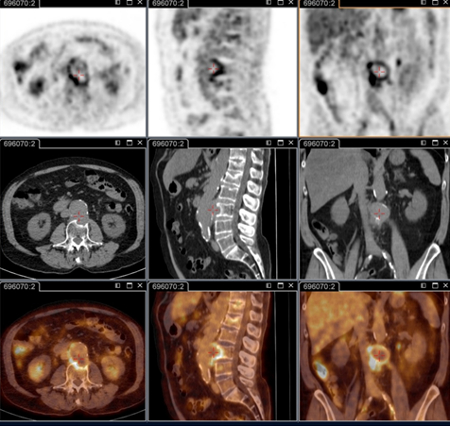

Aneurisma micótico na aorta lombar da febre Q diagnosticado na PET: PET/TC com 18-fluordesoxiglucose. Neste paciente assintomático com história de valva cardíaca e sorologia elevada, a PET permitiu diagnosticar endocardite aórtica na valva nativa com aneurismas micóticos da aorta torácica e lombar

Institut Hospitalo-Universitaire Méditerranée Infection (obtido consentimento do paciente)

Aneurisma micótico na aorta torácica da febre Q diagnosticado na PET: PET/TC com 18-fluordesoxiglucose. Neste paciente assintomático com história de valva cardíaca e sorologia elevada, a PET permitiu diagnosticar endocardite aórtica na valva nativa com aneurismas micóticos da aorta torácica e lombar